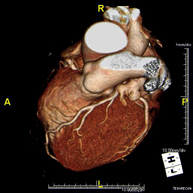

- Angio-TC Cardíaco o TC Cardíaco El angio-TC Cardíaco o Coronariografía no invasiva es una prueba diagnóstica que consiste en el estudio de las arterias del corazón o arterias coronarias mediante el empleo de un equipo de TC Multidetector de última generación y de un contraste yodado, obteniendo imágenes bi y tridimensionales. El TC Multidetector o TCMD permite una adquisición de imágenes tan rápida, que se pueden valorar las arterias coronarias con una alta precisión anatómica: estrechamientos o estenosis, calcificaciones, variantes anatómicas, etc., ya que gracias a su rapidez evita el artefacto que provoca el movimiento constante del corazón (tarda menos de diez segundos en adquirir unas 1000 imágenes). La información obtenida precisa de un tratamiento en estaciones de trabajo con programas especializados en la reconstrucción de las arterias coronarias que permiten valorar el número, la localización y las características de las lesiones. Toda esta información se obtiene de manera no invasiva: solo se requiere la punción de una vena periférica (en el brazo). Es necesario que la frecuencia cardíaca no supere los 75 latidos por minuto, por lo que algunos pacientes deberán realizar un tratamiento previo con un fármaco betabloqueante. El angio-TC Cardíaco o Coronariografía no invasiva es una prueba diagnóstica que consiste en el estudio de las arterias del corazón o arterias coronarias mediante el empleo de un equipo de TC Multidetector de última generación y de un contraste yodado, obteniendo imágenes bi y tridimensionales. El TC Multidetector o TCMD permite una adquisición de imágenes tan rápida, que se pueden valorar las arterias coronarias con una alta precisión anatómica: estrechamientos o estenosis, calcificaciones, variantes anatómicas, etc., ya que gracias a su rapidez evita el artefacto que provoca el movimiento constante del corazón (tarda menos de diez segundos en adquirir unas 1000 imágenes). La información obtenida precisa de un tratamiento en estaciones de trabajo con programas especializados en la reconstrucción de las arterias coronarias que permiten valorar el número, la localización y las características de las lesiones. Toda esta información se obtiene de manera no invasiva: solo se requiere la punción de una vena periférica (en el brazo). Es necesario que la frecuencia cardíaca no supere los 75 latidos por minuto, por lo que algunos pacientes deberán realizar un tratamiento previo con un fármaco betabloqueante.

- Angio TC cardíac L'Angio TC cardíac o la coronariografia no invasiva és una prova diagnòstica que consisteix en l'estudi de les artèries del cor o artèries coronàries mitjançant l'ús d'un equip de TC Multidetector d'última generació (64 corones o files de detectors) i de contrast iodat amb l'obtenció d'imatges bi i tridimensionals. El TC Multidetector 64 o TCMD64 permet una adquisició d'imatges tan ràpida que es poden valorar les artèries coronàries amb alta precisió anatòmica (estrenyiments o estenosis, calcificacions, variants anatòmiques, etc.), ja que, gràcies a la seva rapidesa, evita les falses imatges que provoca el moviment constant del cor (triga menys de deu segons en adquirir unes 1000 imatges). La informació obtinguda d'un tractament en estacions de treball amb programes especialitzats en la reconstrucció de les artèries coronàries que permeten valorar el nombre, la localització i les característiques de les lesions. Tota aquesta informació s'obté de manera no invasiva: només es necessita la punció d'una vena perifèrica (en el braç). És necessari que la freqüència cardíaca no superi els 75 batecs per minut, per això els pacients han de realitzar un tractament previ amb un fàrmac betabloquejant. L'Angio TC cardíac o la coronariografia no invasiva és una prova diagnòstica que consisteix en l'estudi de les artèries del cor o artèries coronàries mitjançant l'ús d'un equip de TC Multidetector d'última generació (64 corones o files de detectors) i de contrast iodat amb l'obtenció d'imatges bi i tridimensionals. El TC Multidetector 64 o TCMD64 permet una adquisició d'imatges tan ràpida que es poden valorar les artèries coronàries amb alta precisió anatòmica (estrenyiments o estenosis, calcificacions, variants anatòmiques, etc.), ja que, gràcies a la seva rapidesa, evita les falses imatges que provoca el moviment constant del cor (triga menys de deu segons en adquirir unes 1000 imatges). La informació obtinguda d'un tractament en estacions de treball amb programes especialitzats en la reconstrucció de les artèries coronàries que permeten valorar el nombre, la localització i les característiques de les lesions. Tota aquesta informació s'obté de manera no invasiva: només es necessita la punció d'una vena perifèrica (en el braç). És necessari que la freqüència cardíaca no superi els 75 batecs per minut, per això els pacients han de realitzar un tractament previ amb un fàrmac betabloquejant.